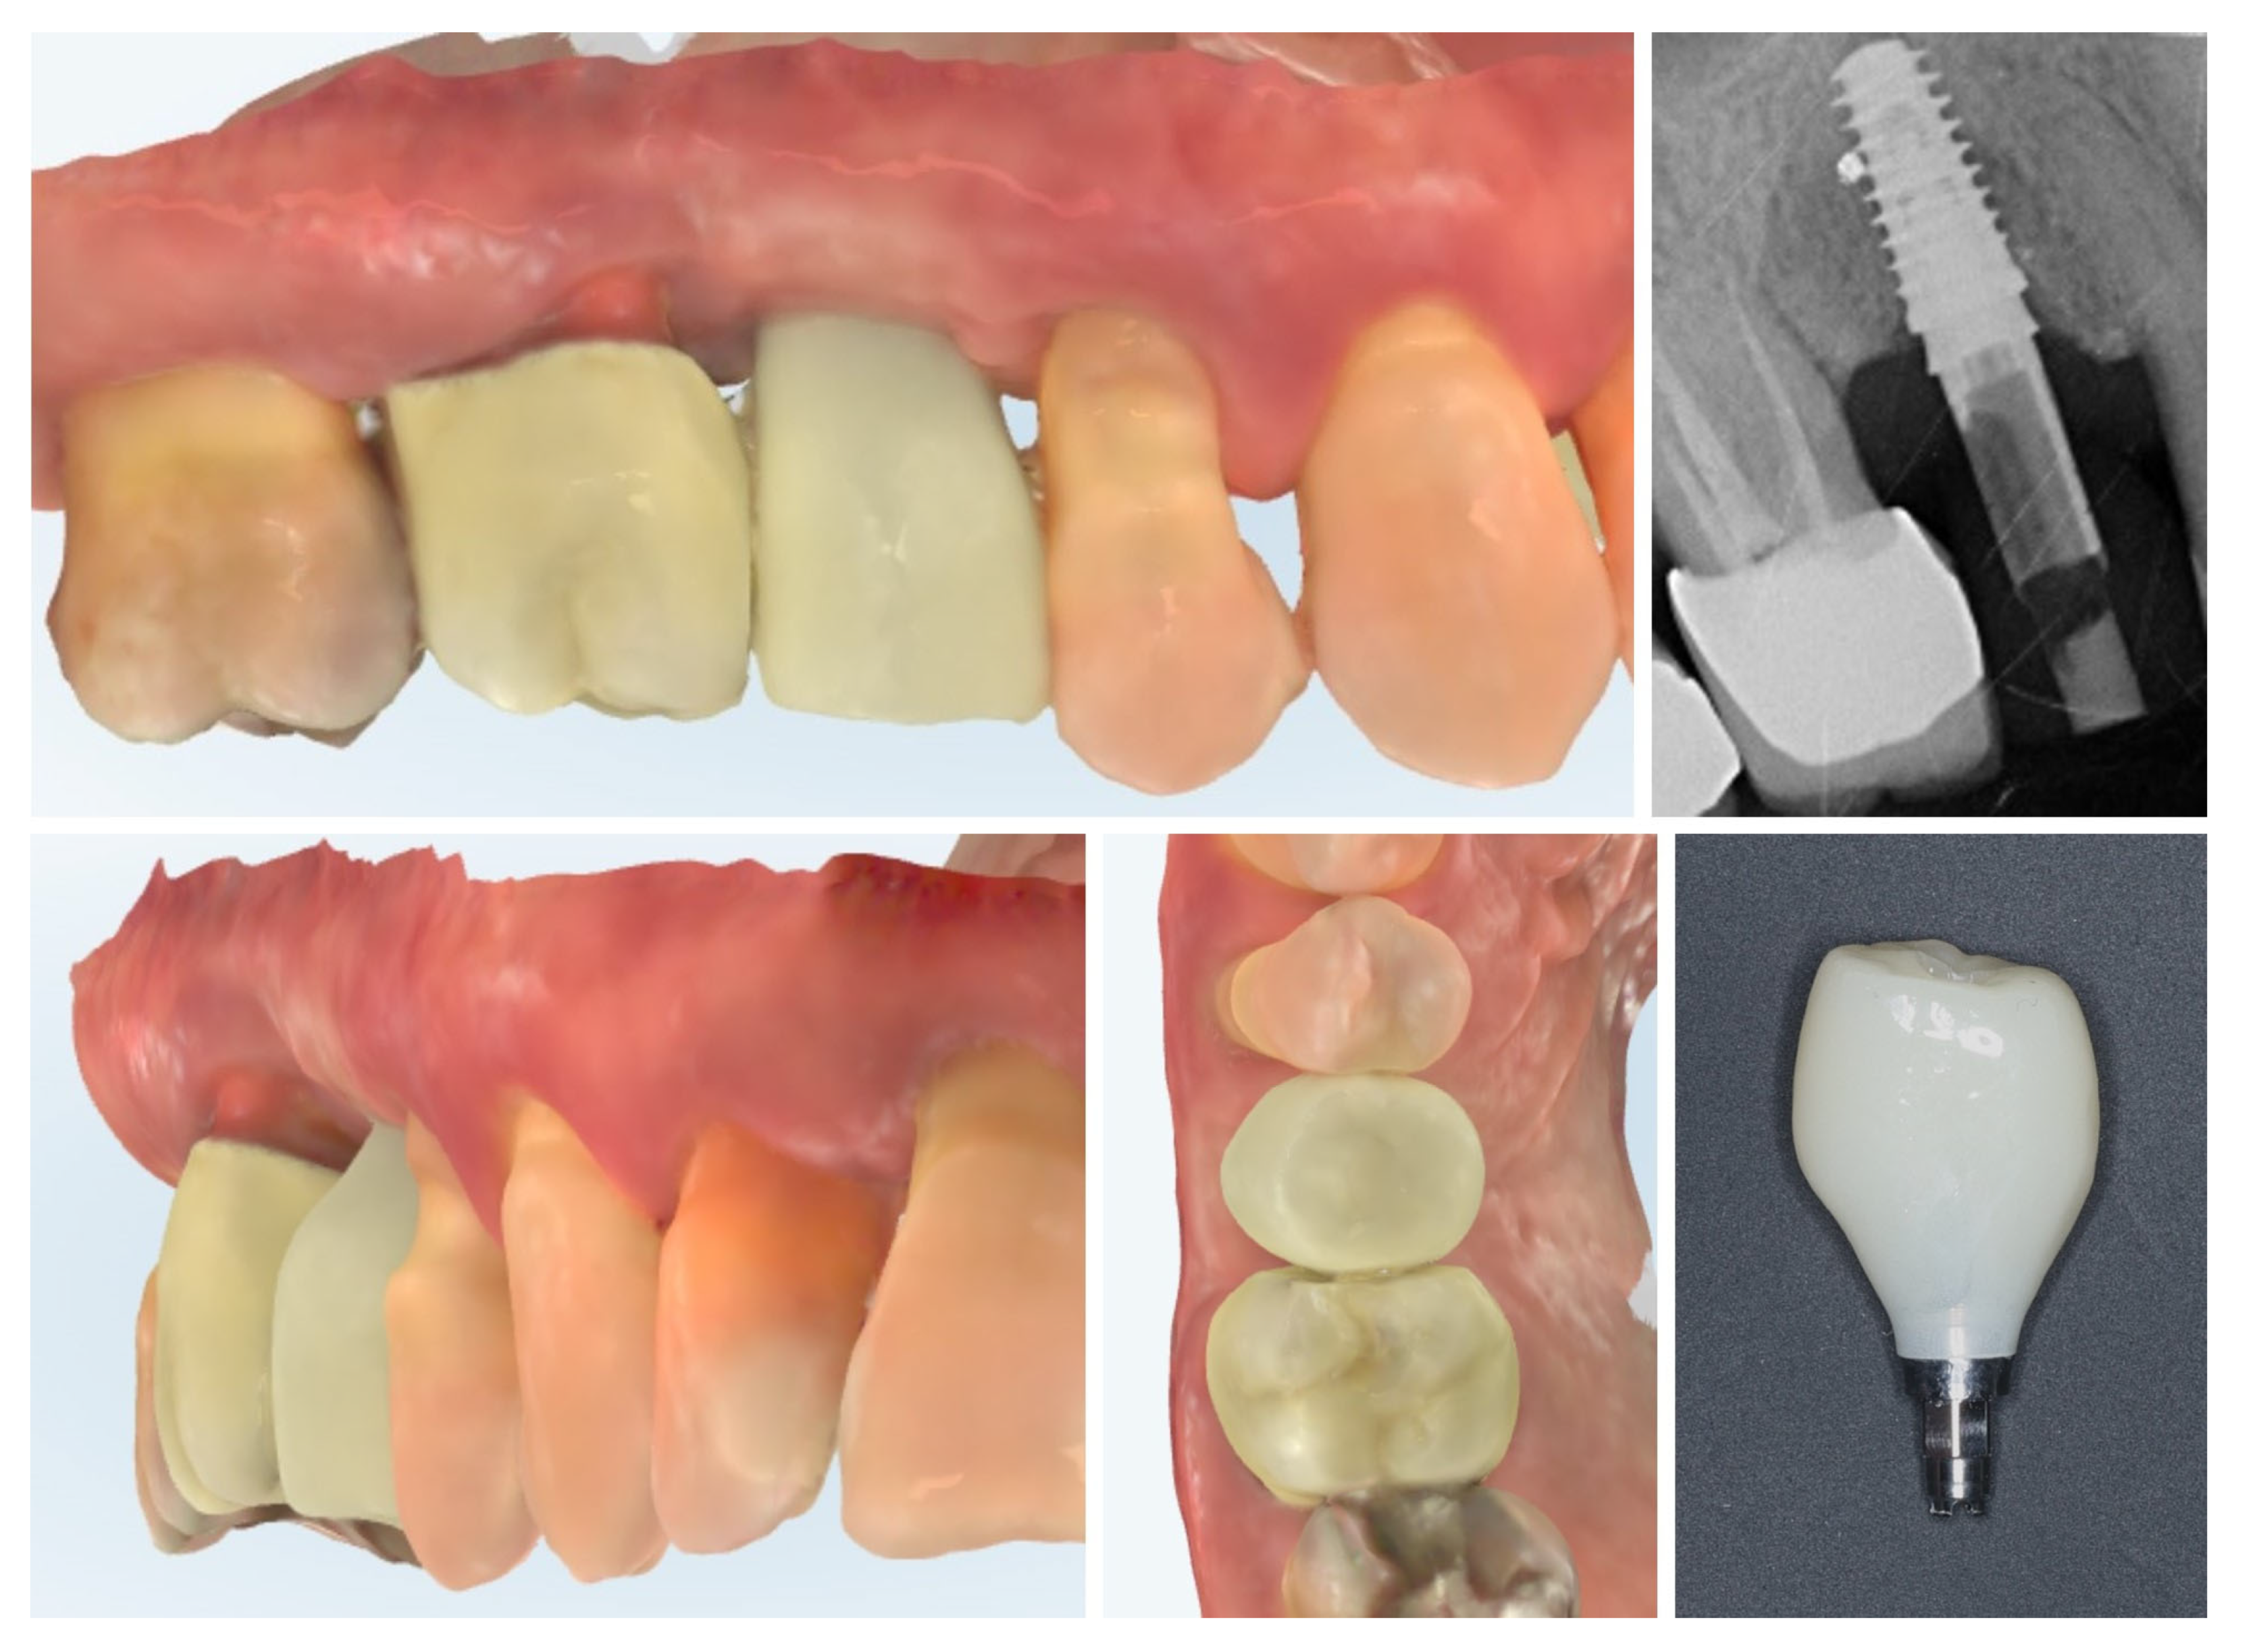

The clinical workflow progressed to digital impression of the multi-purpose healing abutment and provisional crown fabrication. The emergence profile of the Ti-base and the transmucosal part of the crown follows the profile of the healing abutment exactly, thus avoiding any changes in the critical contour zone of the transmucosal area in order to avoid any crestal bone remodelling after placement of the provisional crown. Intraoral scans (upper and lower rows) confirm the stable peri-implant mucosal margin achieved through roll flap augmentation, providing favourable conditions for an esthetic emergence profile (Figure 13).

Figure 13.

Digital impressions and provisional crown fabrication (3 months post-op).

One month after provisionalization, intraoral scans demonstrate stable peri-implant soft tissue contours around the temporary crown. The mucosal margin exhibits favourable adaptation and maturation, with preservation of the buccal volume achieved through roll flap augmentation. The temporary restoration supports the peri-implant mucosa, guiding the emergence profile for the definitive prosthesis (Figure 14.).

Figure 14.

Intraoral scan 1 month after provisional crown placement (4 months post-op).

At 4 months after provisional crown placement, clinical examination reveals stable peri-implant soft tissues with a healthy mucosal margin and increased buccal and interdental soft tissue thickness around the temporary crown. The soft tissue integration demonstrates maturation and stability, with no signs of inflammation, recession, or dehiscence. Radiographic evaluation (right) confirms proper implant positioning with intimate bone-to-implant contact and preservation of crestal bone levels, indicating successful osseointegration and tissue stability at this stage of provisionalization (Figure 15.).

Figure 15.

Clinical and radiographic evaluation at 4 months with provisional crown (7 months post-op).

Clinical views of the implant site prior to final prosthetic restoration show a well-formed peri-implant mucosal collar with healthy soft tissue contours. The buccal mucosa demonstrates adequate thickness, consistent with the roll flap augmentation performed at the time of implant placement. The soft tissue margin appears stable without signs of inflammation, ensuring favourable conditions for the subsequent impression and definitive crown placement (left). The comparison with the situation before placement of the provisional crown (right) shows the increase in the soft tissue volume induced by the emergence profile of the crown (Figure 16).

Figure 16.

Peri-implant mucosal contours prior to definitive restoration (8 months post-op).

Digital scans obtained at delivery of the definitive prosthetic reconstructions show stable integration of both the implant-supported crown in region 15 and the full-contour zirconia crown on tooth 16 (Figure 17). The emergence profile of the implant-supported crown completely copies the profile of the temporary crown in order to not induce changes in the crestal bone. The peri-implant soft tissues demonstrate healthy contours and harmonious adaptation to the restoration’s emergence profile. The occlusal and proximal relationships are well-preserved, ensuring functional loading and esthetic integration with adjacent teeth. No soft tissue recession or volumetric loss is evident, confirming the stability of the roll flap augmentation and the favourable outcome of the prosthetic phase.

Figure 17.

Clinical view of the final implant-supported and tooth-supported crowns (8 months post-op).